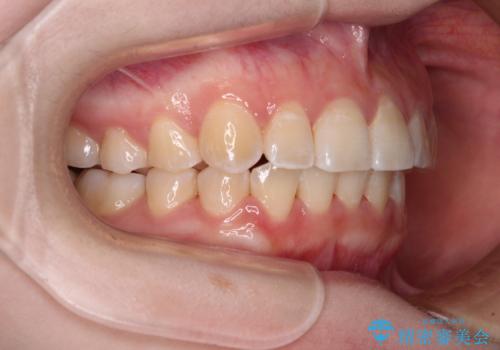

【モニター】前歯のデコボコを目立たないワイヤー装置で短期間矯正治療

- 上下前歯のデコボコを気にして来院された患者様です。

患者様も驚く、僅か10か月での治療終了となりました。

下顎前歯が1歯欠損しているため、上下正中は合わず、左右奥歯の咬み合わせは理想的とはならない仕上がりとなります。